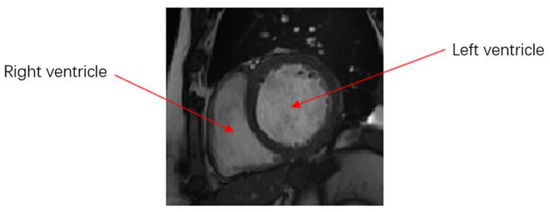

At present, cardiac MR imaging is one of the most important, accurate, and noninvasive diagnostic tools for imaging cardiac structure and function. Doctors usually analyze a patient’s cardiac MR images and calculate the continuous dynamic changes in the left and right ventricular volumes in the process of contraction and relaxation. This approach can be used to determine parameters, such as cardiac end-diastolic and -systolic volume, stroke output, and ejection fraction, to judge an individual’s cardiovascular health status. Therefore, accurate segmentation of ventricles in such imaging is very important. A cardiac MR image is shown in Figure 1.

Figure 1. MR image of the heart.